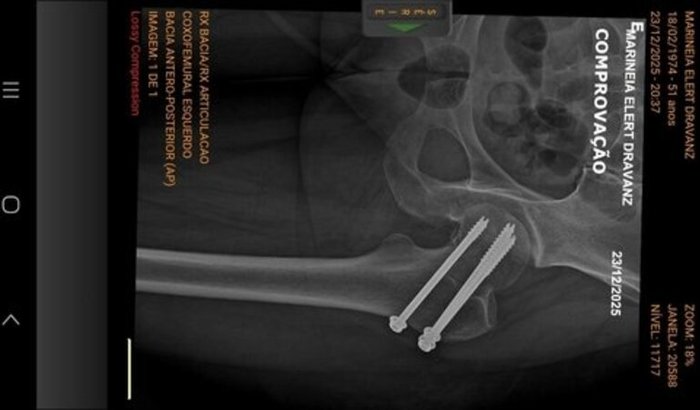

Olá, meu nome é Marineia Elert Dravanz e moro em Pelotas (RS). Recentemente, enfrentei um acidente que resultou em uma fratura no meu fêmur, e a indicação médica para meu tratamento exige uma cirurgia urgente. Estou buscando apoio para arcar com os custos hospitalares, honorários médicos, materiais e a recuperação adequada. A intervenção cirúrgica é essencial para que eu possa voltar a caminhar e retomar minhas atividades diárias com segurança. Além da operação, precisarei de sessões de fisioterapia e acompanhamento pós‐operatório, o que envolve despesas adicionais de transporte e cuidados especializados. Cada contribuição faz a diferença e me aproxima do meu objetivo de recuperar totalmente minha mobilidade. Se você puder ajudar, por favor, utilize a chave PIX abaixo. Pix: 5862808@vakinha.com.br Qualquer valor será recebido com muita gratidão e contribui diretamente para o meu tratamento. Agradeço de coração pela solidariedade, pelo compartilhamento desta campanha e pelo carinho de cada um. Muito obrigada!